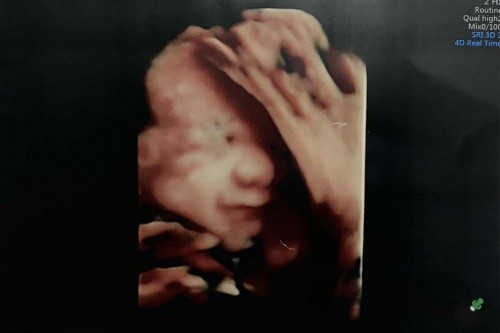

30+6week จ้าาา❤️

29+1 wks ค่ะ ตอนนี้ 32 wks แล้ว